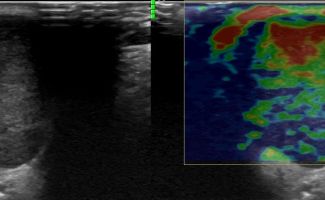

Το υψηλής ευκρίνειας Έγχρωμο Υπερηχογράφημα Σιελογόνων Αδένων με την τεχνική της Ελαστογραφικής Μελέτης μπορεί να διαγνώσει αξιόπιστα παθολογίες όπως;

Η αξιοπιστία του Υπερηχογραφήματος στη διάγνωση παθολογίας των Σιελογόνων Αδένων έχει καθιερωθεί τα τελευταία χρόνια και εξασφαλίζεται με τη χρήση Υπερηχογράφων τελευταίας γενιάς με ειδικούς υψίσυχνους ηχοβολείς και με την εξοικείωση και εμπειρία του εξεταστή-ιατρού με την ηχοανατομία και παθολογία των Σιελογόνων Αδένων και της περιοχής κεφαλής – τραχήλου.